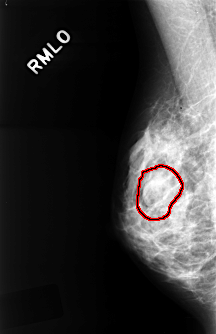

C_0327_1.RIGHT_MLO

RIGHT_MLO LINES 4336 PIXELS_PER_LINE 2808 BITS_PER_PIXEL 12 RESOLUTION 50 OVERLAY

FILE: C_0327_1.RIGHT_MLO.OVERLAY

TOTAL_ABNORMALITIES 1

ABNORMALITY 1

LESION_TYPE MASS SHAPE OVAL MARGINS OBSCURED

ASSESSMENT 3

SUBTLETY 4

PATHOLOGY BENIGN

TOTAL_OUTLINES 1

BOUNDARY